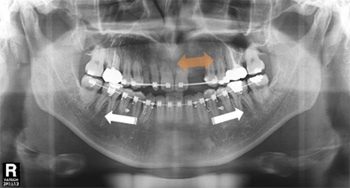

아랫니가 앞니보다 바깥쪽으로 위치한 증상을 바로잡고 빠진 윗니를 수복하기 위해 내원한 37세 남성입니다.

검사 결과 위쪽 영구치 3개 결손 된 상태였으며, 아래턱이 전방 위치된 주걱턱(골격성 3급 부정교합)으로 진단

하였으나 양악수술 없이 치료를 원하셔서 치아교정과 임플란트 치료를 병행하였습니다.

약 2년 간의 교정 치료 후 정상적인 앞니 배열과 임플란트 식립에 필요한 공간이 확보되어 보철 치료를 한 후

교정 장치를 제거하였습니다. 거꾸로 물려 정상적인 기능이 어려웠던 앞니의 심미적, 기능적 회복이 동시에

이루어졌습니다.